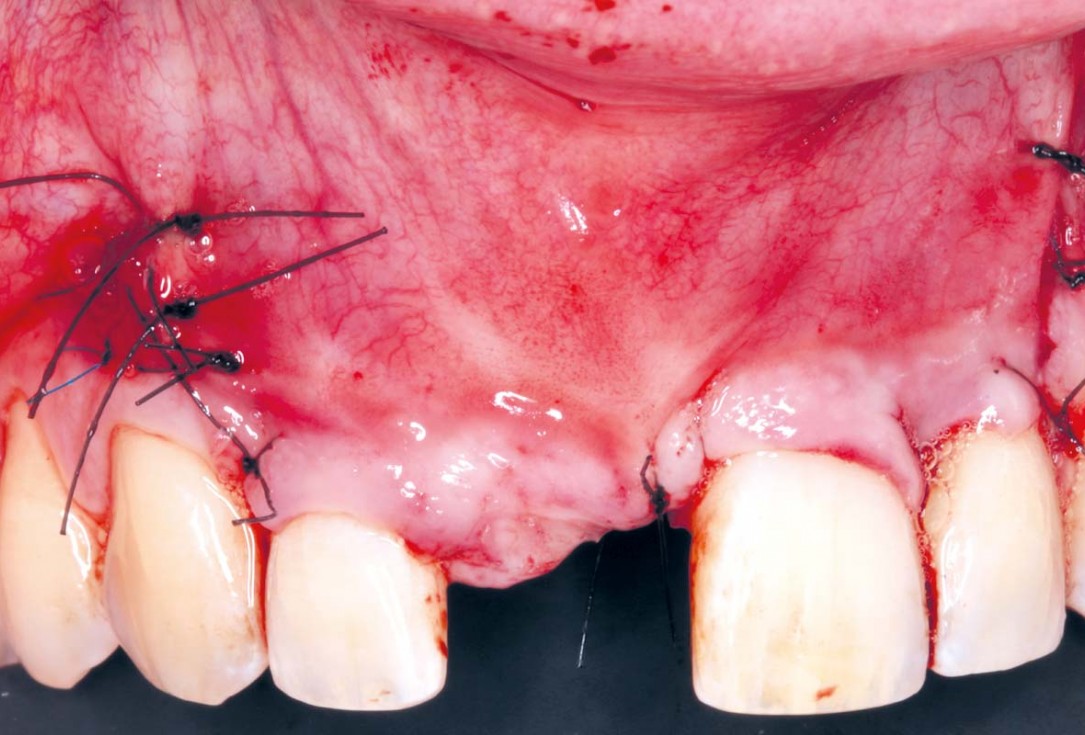

08/20 - Wound closure without tension and without having to make extra incisions.Delayed implant placement with GBR and soft tissue augmentation at the aesthetic area - 2 years follow up – Dr. H. Maghaireh & Dr. V. Ivancheva

09/20 - Wound closure without tension and without having to make extra incisions.Delayed implant placement with GBR and soft tissue augmentation at the aesthetic area - 2 years follow up – Dr. H. Maghaireh & Dr. V. Ivancheva